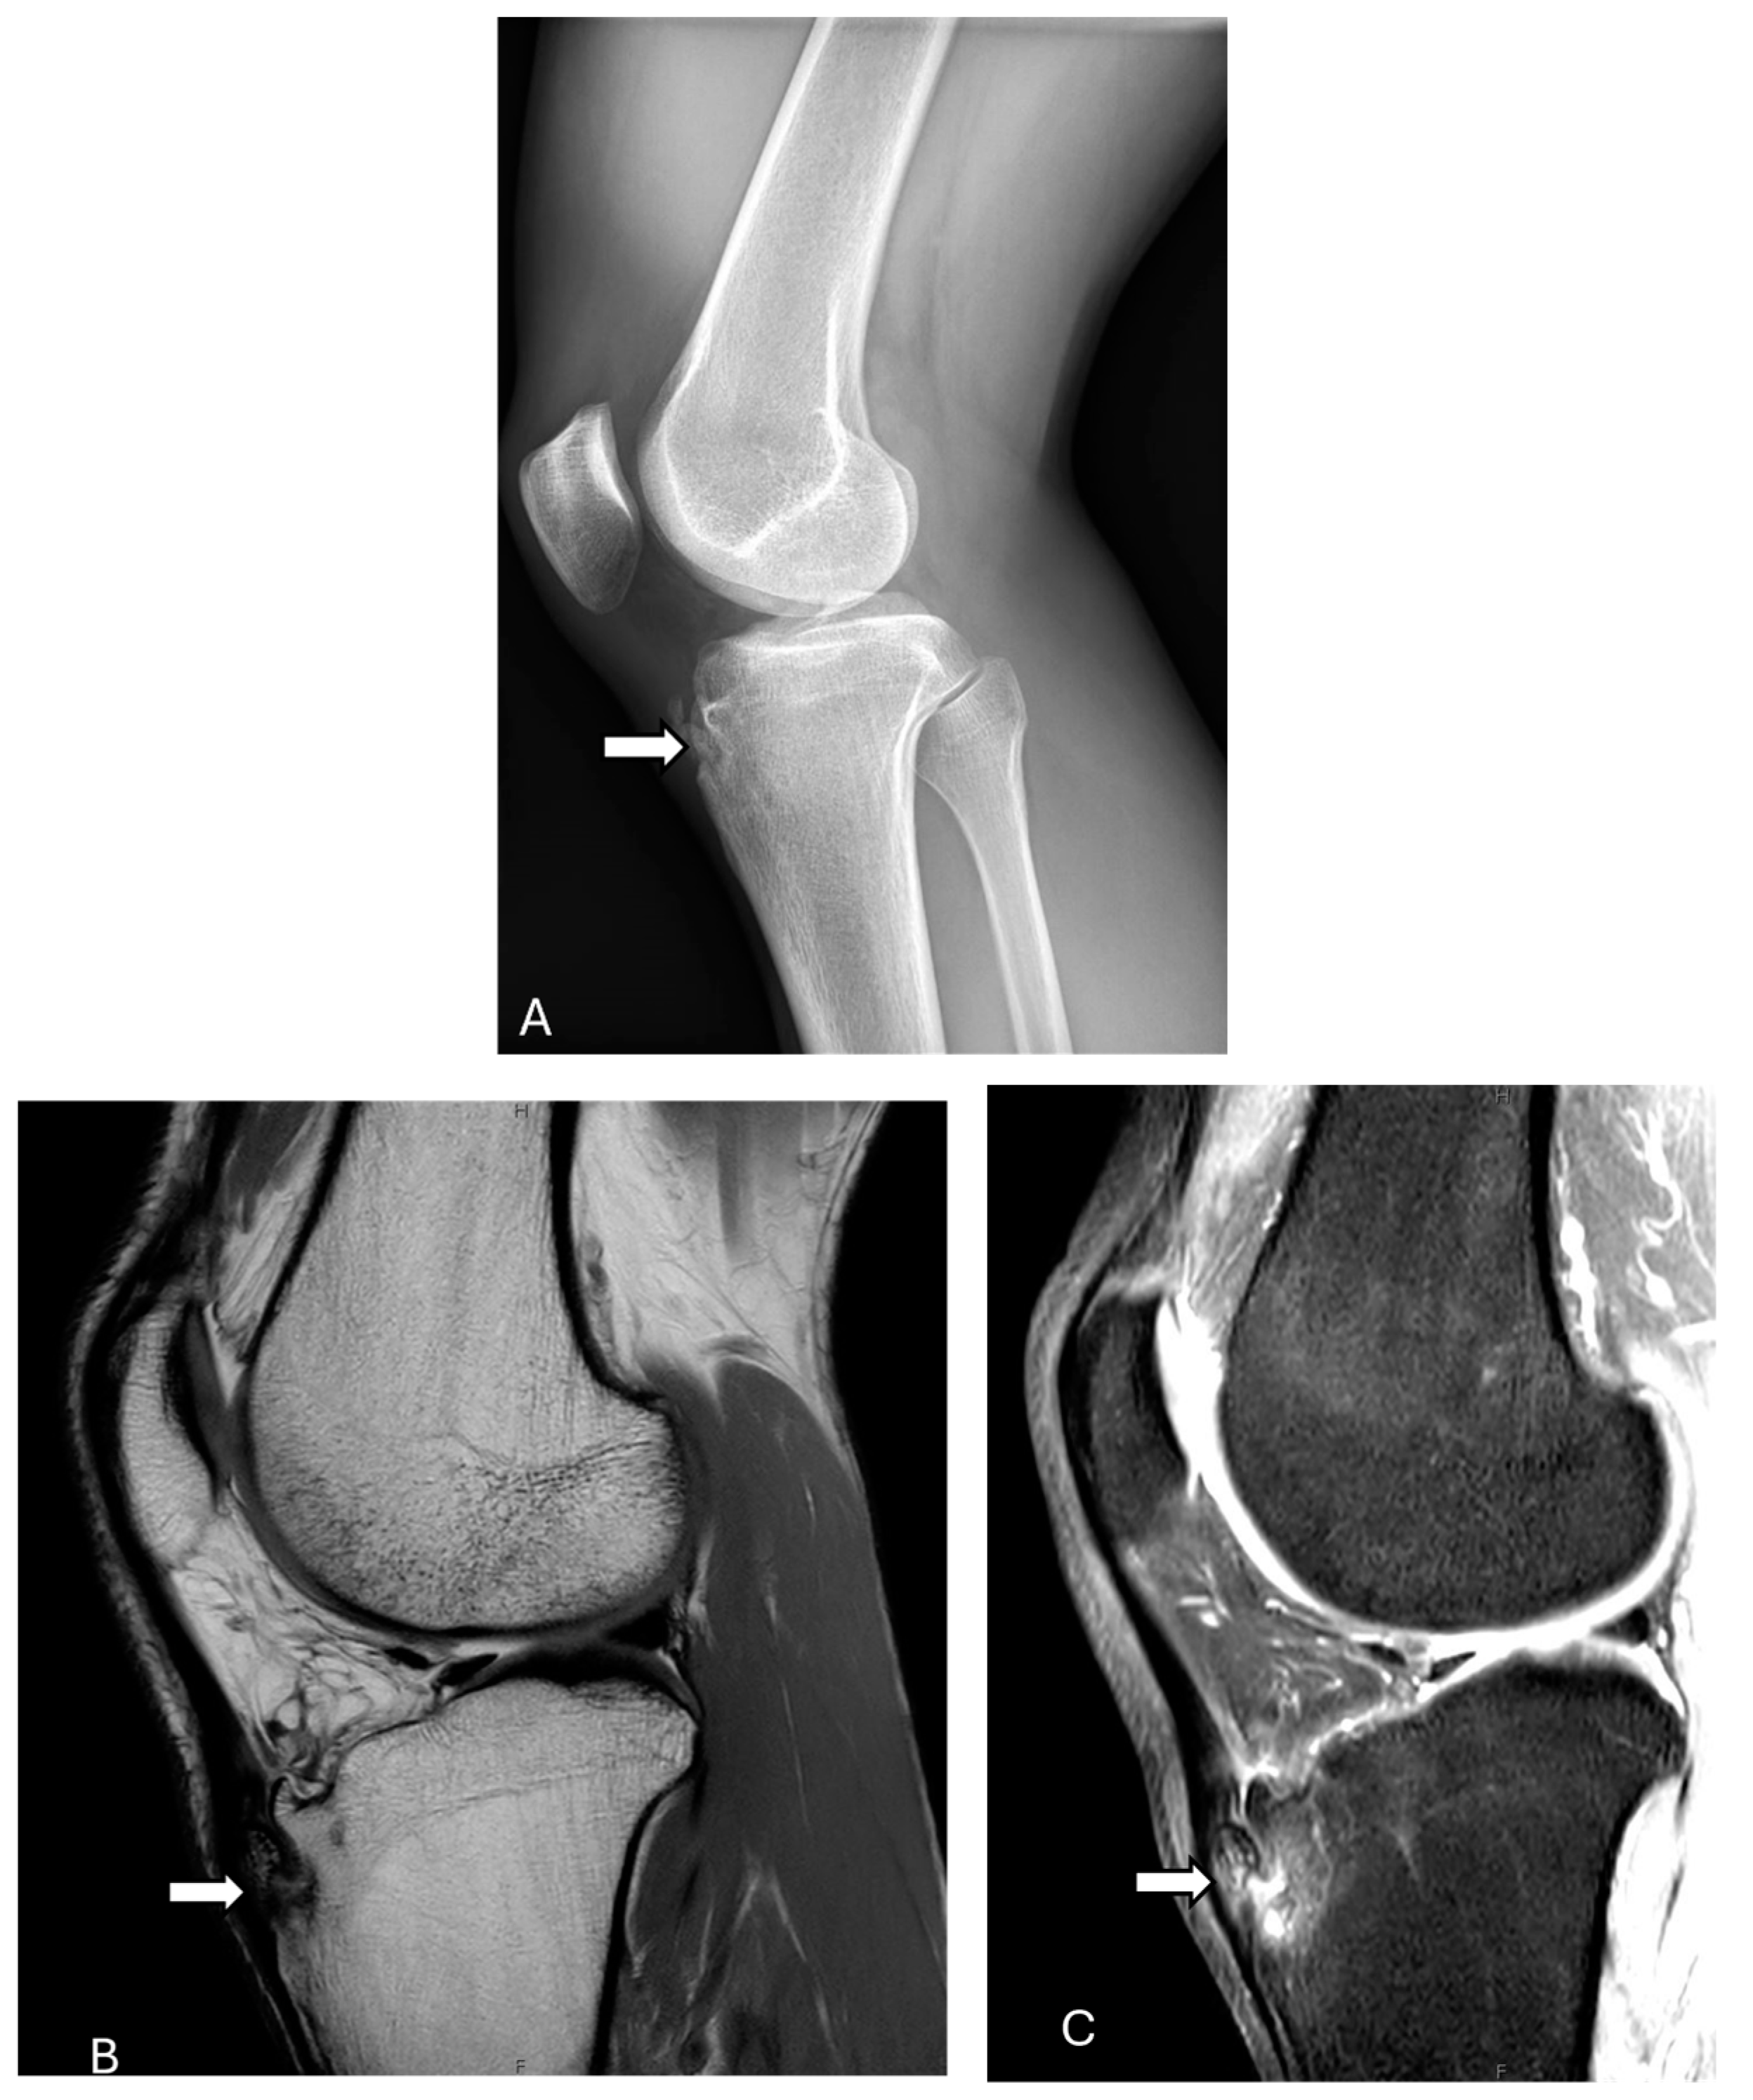

2.2. Dorsal Defect of the Patella